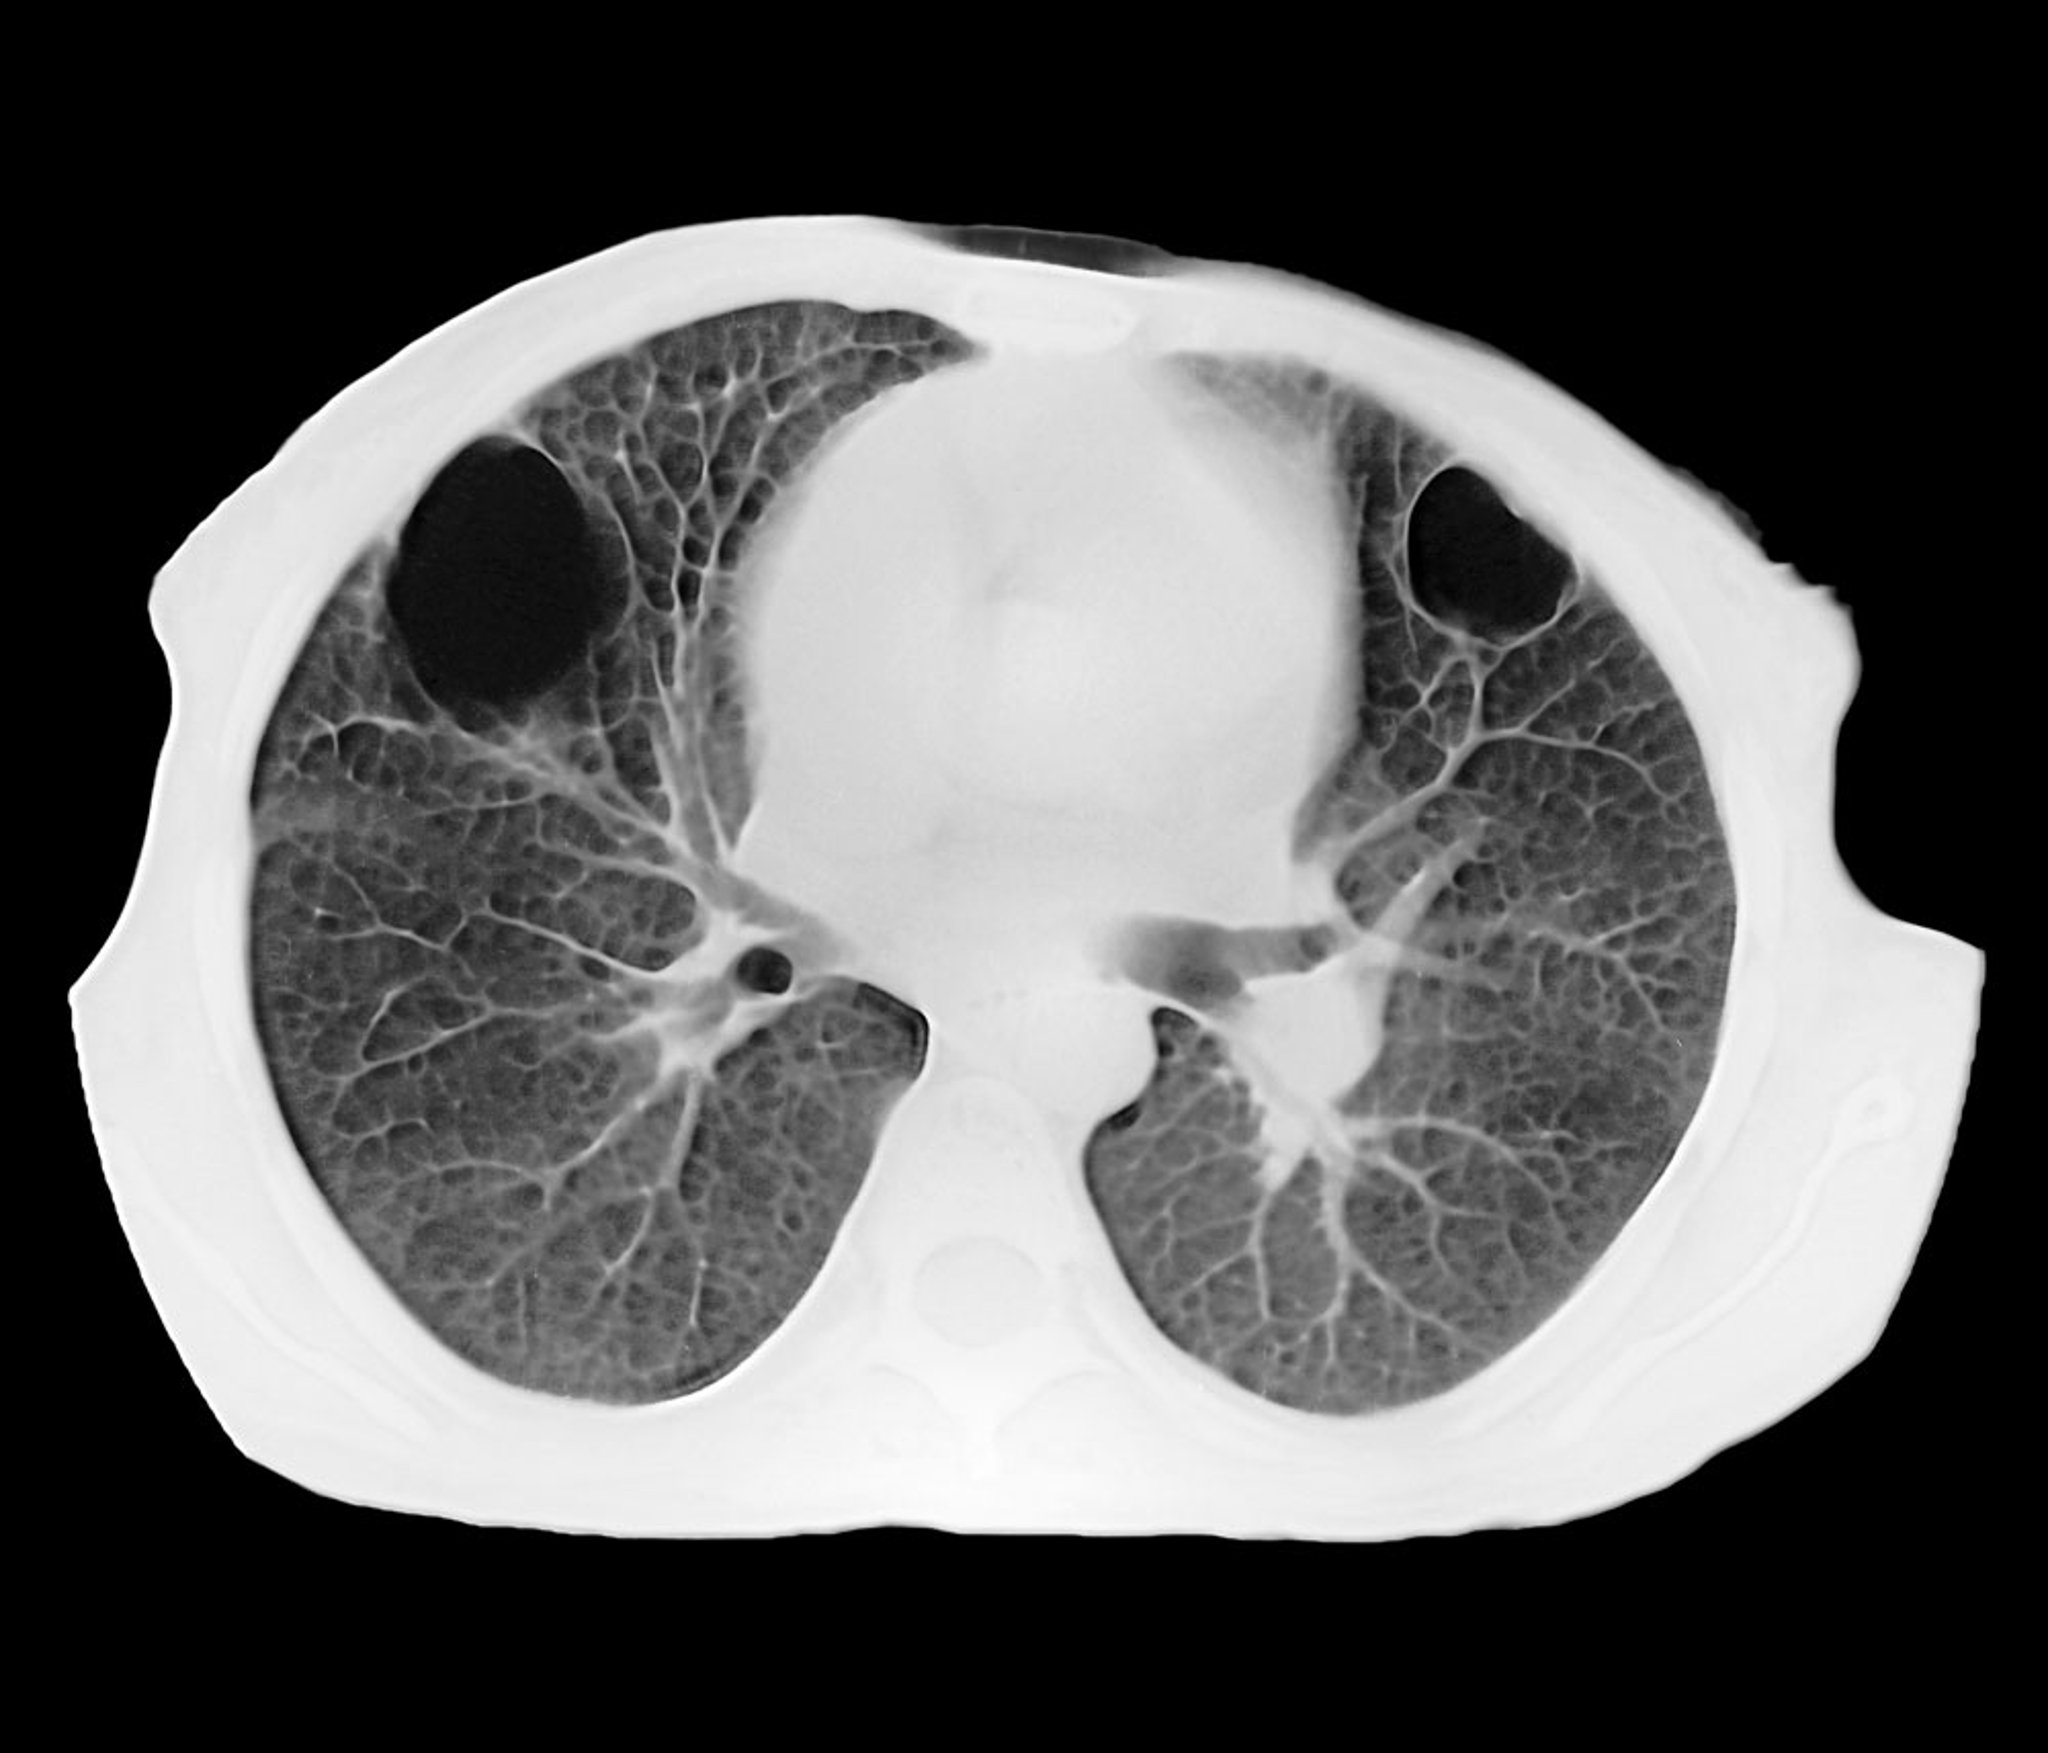

Ascesso polmonare (TC)

Questa TC assiale mostra 2 ascessi polmonari parenchimali ben circoscritti nei lobi anteriore destro e sinistro. L'interno nero corrisponde a un accumulo di pus.